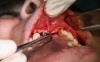

Fig 1. Tooth extraction resulted in a defected wall.

Figure 1